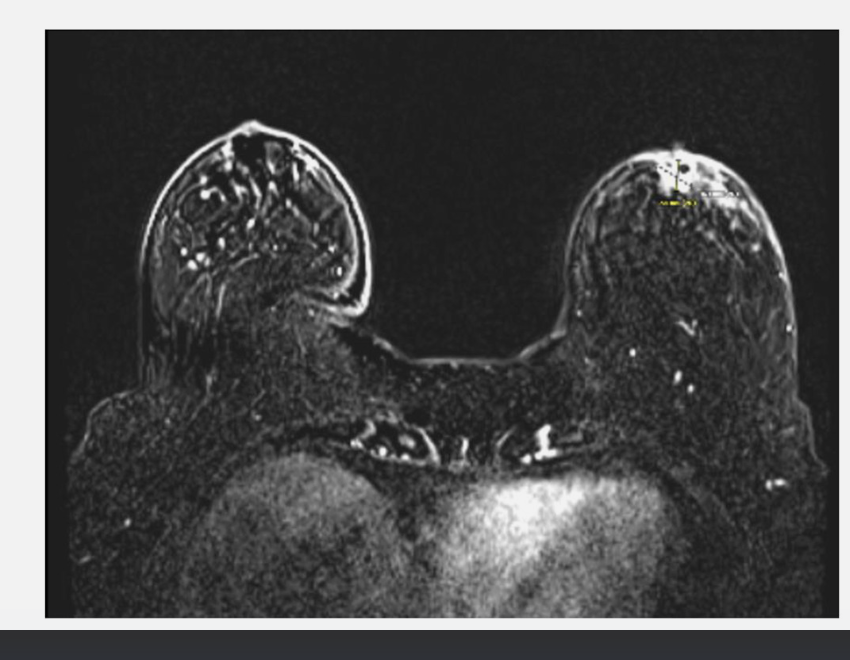

T2 MRI, CT simulation, and Cone Beam CT showing prostatic calculi used for image guidance

Multiparametric prostate MRI-based intensity-modulated radiation therapy guided by prostatic calcifications. (a) T2 MRI demonstrating an 8 mm PI-RADS 4 nodule in the right apex with superimposed dose distribution delivering 81 Gy to the prostate nodule, 77.4 Gy to the prostate and 70 Gy to the prostate and proximal seminal vesicles with additional margin. (b) CT simulation demonstrating two calcifications in the mid prostate. (c) Cone beam CT demonstrating prostatic calculi in the mid-prostate.